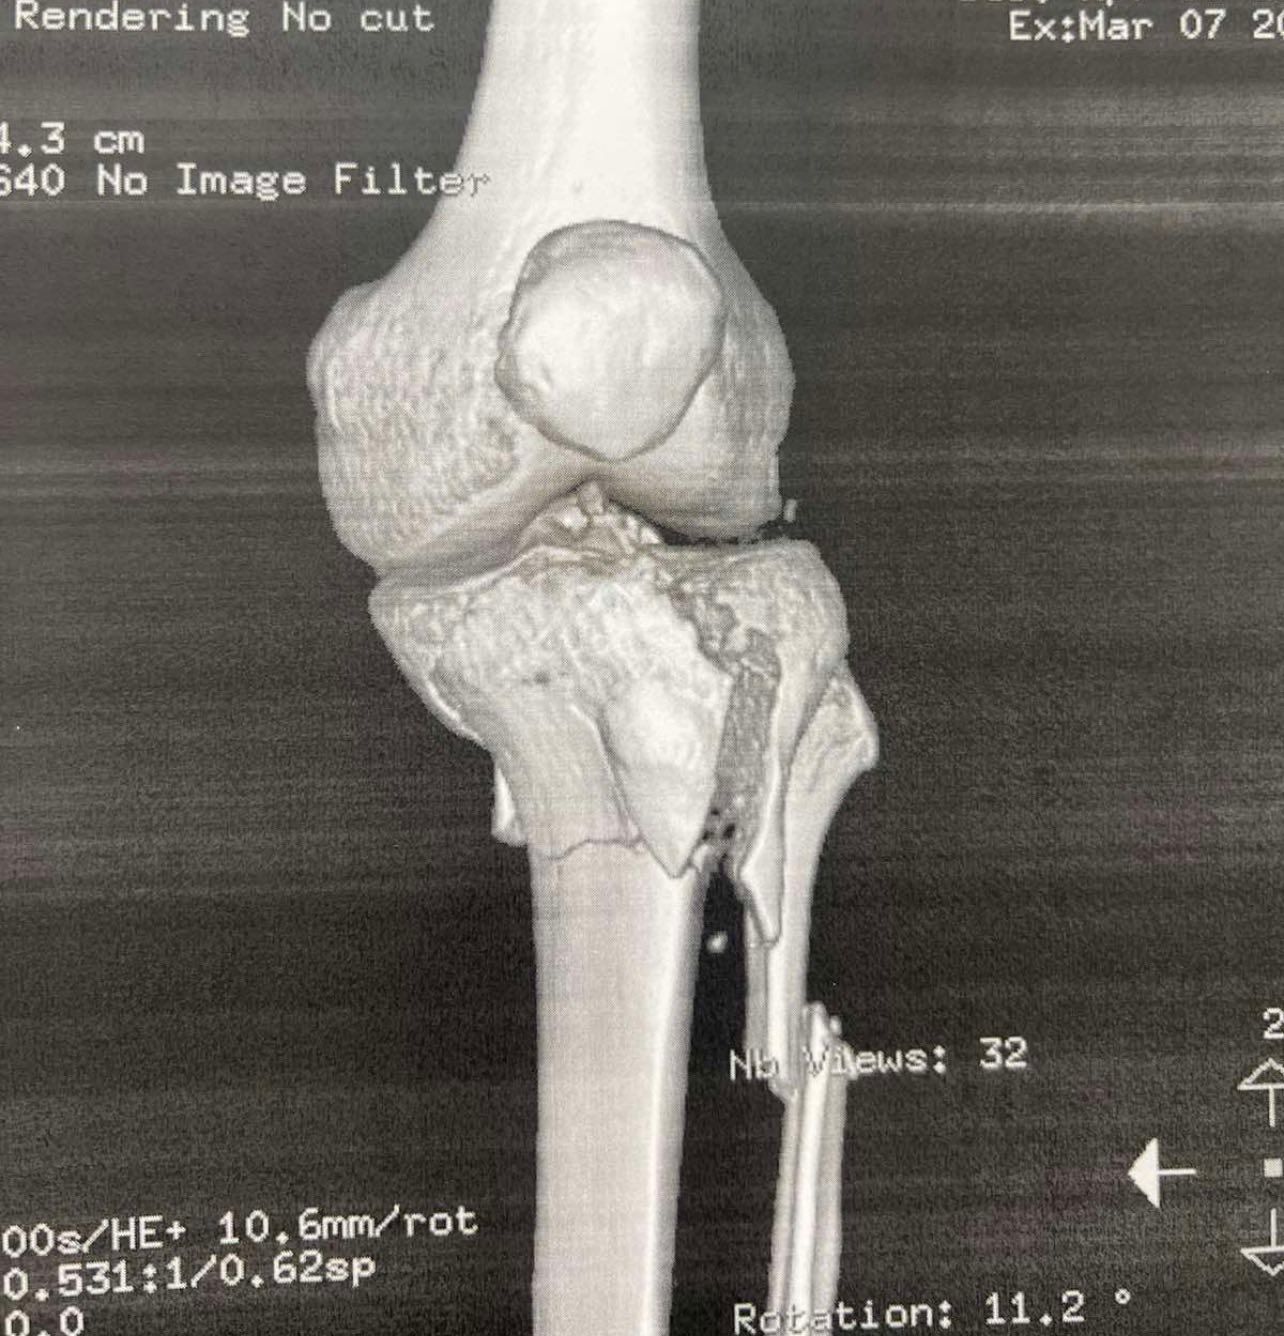

Πριν το χειρουργείο (απεικονίσεις τραυματισμού)

Ο Schatzker τύπος VI είναι από τις πιο βαριές κακώσεις: πρόκειται για κάταγμα του πλατώ με μεταφυσιο-διαφυσιακή ασυνέχεια(δηλαδή «διαχωρισμό» της μεταφύσεως από τη διάφυση), συχνά μετά από υψηλής ενέργειας τραυματισμό. Τέτοιες κακώσεις μπορεί να συνοδεύονται από σημαντικό οίδημα/βλάβες μαλακών μορίων και απαιτούν ιδιαίτερη προσοχή στον χρόνο και στον τρόπο αποκατάστασης.